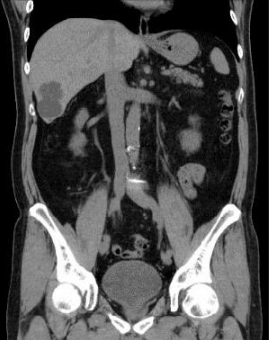

全新32排16層 CT 裝置 Apsaras。新産品全面改善常規的工作流程,完善各項臨床應用的功能。在确保極低的輻射劑量同時提高效率,關愛患者。

Apsaras 是具有全面表現力的 CT 系統,新産品其傑出的掃描能力及自主研發的臨床軟件的應用使産品集疾病的診斷、治療、預防爲一體,考慮醫生、使用者、受檢者的多重需要,開拓了全新的醫學領域。适用于急診、門診、病房以及臨床科研的全方位應用。